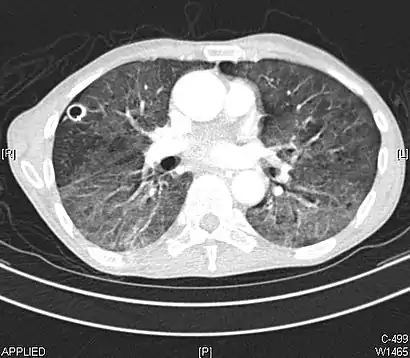

CT image in patient with COVID-19 showing bilateral ground-glass opacities at the periphery of both lungs.

Ground-glass opacity is among the most common imaging findings in patients with confirmed COVID-19.[16][17] One systematic review found that among patients with COVID-19 and abnormal lung findings on CT, greater than 80% had GGOs, with greater than 50% having mixed GGOs and consolidation.[16] GGOs with mixed consolidation has most often been found in elderly populations.[18] Several studies have described a pattern among initial, intermediate, and hospital discharge imaging findings in the disease course of COVID-19. Most commonly, initial CT imaging reveals bilateral GGOs at the periphery of the lungs. During initial stages, this is most often found in the lower lobes, although involvement of the upper lobes and right middle lobe has also been reported early in the disease course.[16][18] This is in contrast to the two similar coronaviruses, SARS and MERS, which more commonly involve only one lung on initial imaging.[19][20] As the COVID-19 infection progresses, GGOs typically become more diffuse and often progress to consolidation.[11][18] This is sometimes accompanied by the development of a crazy paving pattern and interlobular septal thickening.[18] In many cases the most severe pulmonary CT abnormalities occurred within 2 weeks after symptoms began.[17] At this point, many individuals begin showing resolution of consolidation and GGOs as symptoms improve. However, some patients have worsening symptoms and imaging findings, with further increase in septal thickening, GGOs, and consolidation. These patients may develop lung "white-out" with progression to acute respiratory distress syndrome (ARDS) requiring treatment escalation.[17][21]

Preliminary reports have shown many patients have residual GGOs at time of discharge from the hospital. Due to the novelty of COVID-19, large studies investigating the long-term pulmonary CT changes have yet to be completed. However, long-term pulmonary changes have been seen in patients after recovery from SARS and MERS, suggesting the possibility of similar long-term complications in patients who have recovered from acute COVID-19 infection.[22]